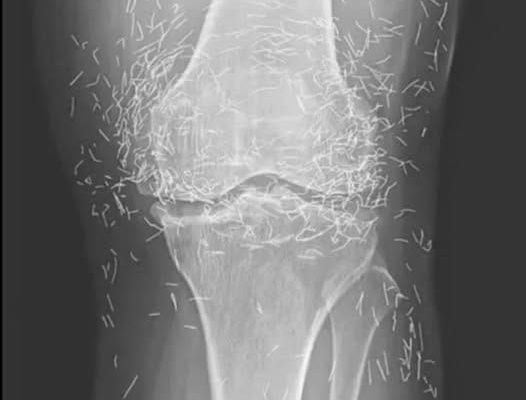

A 65-year-old woman came to the clinic after experiencing months of chronic knee pain

Years later, when doctors took X-rays to evaluate her knee condition, they weren’t prepared for what appeared on the images. Her knees were filled with dozens of bright, metallic flecks — tiny needles embedded deep within the joint area.

The findings were later documented in a case published by the New England Journal of Medicine.

While striking, the discovery raised immediate concerns.

Beyond inflammation, the needles created another problem: imaging complications. Metal objects can obscure parts of the anatomy on X-rays, making it harder for doctors to clearly assess joint damage or disease progression.

Even more concerning, the presence of metal inside the body can make certain scans dangerous. MRI machines rely on powerful magnetic fields, and embedded needles may shift during scanning, potentially damaging blood vessels or surrounding tissue. In short, future diagnostic options for this patient became limited.